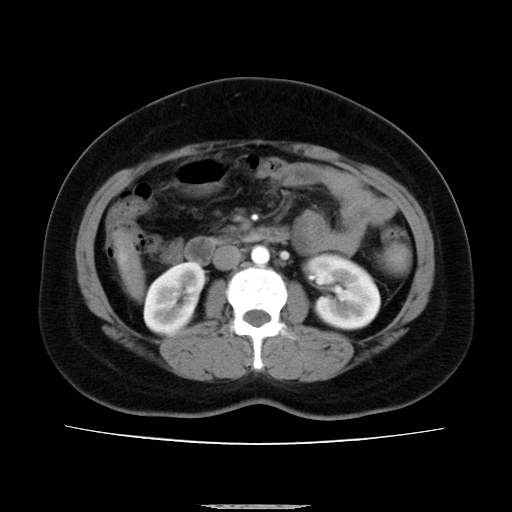

标题: CT14225:女性46岁。当地B超示肝内占位,来我院作CT检查。请 [打印本页]

标题: CT14225:女性46岁。当地B超示肝内占位,来我院作CT检查。请

肝内结节强化特点符合原发性肝癌表现,脾脏改变考虑为增大及先天发育所致。

动脉期病原灶明显强化高于肝密度且中央有无强化区,静脉期强化程度下降明显,延迟低于肝密度,考虑肝腺瘤可能性大,

肝内结节强化特点:快进快出符合原发性肝癌表现

此患者虽然符合快进的特点,却不符合快出的特点,因为门脉期几乎是等密度,不符合肝癌的增强表现,所以我考虑肝局灶性结节增生可能性大